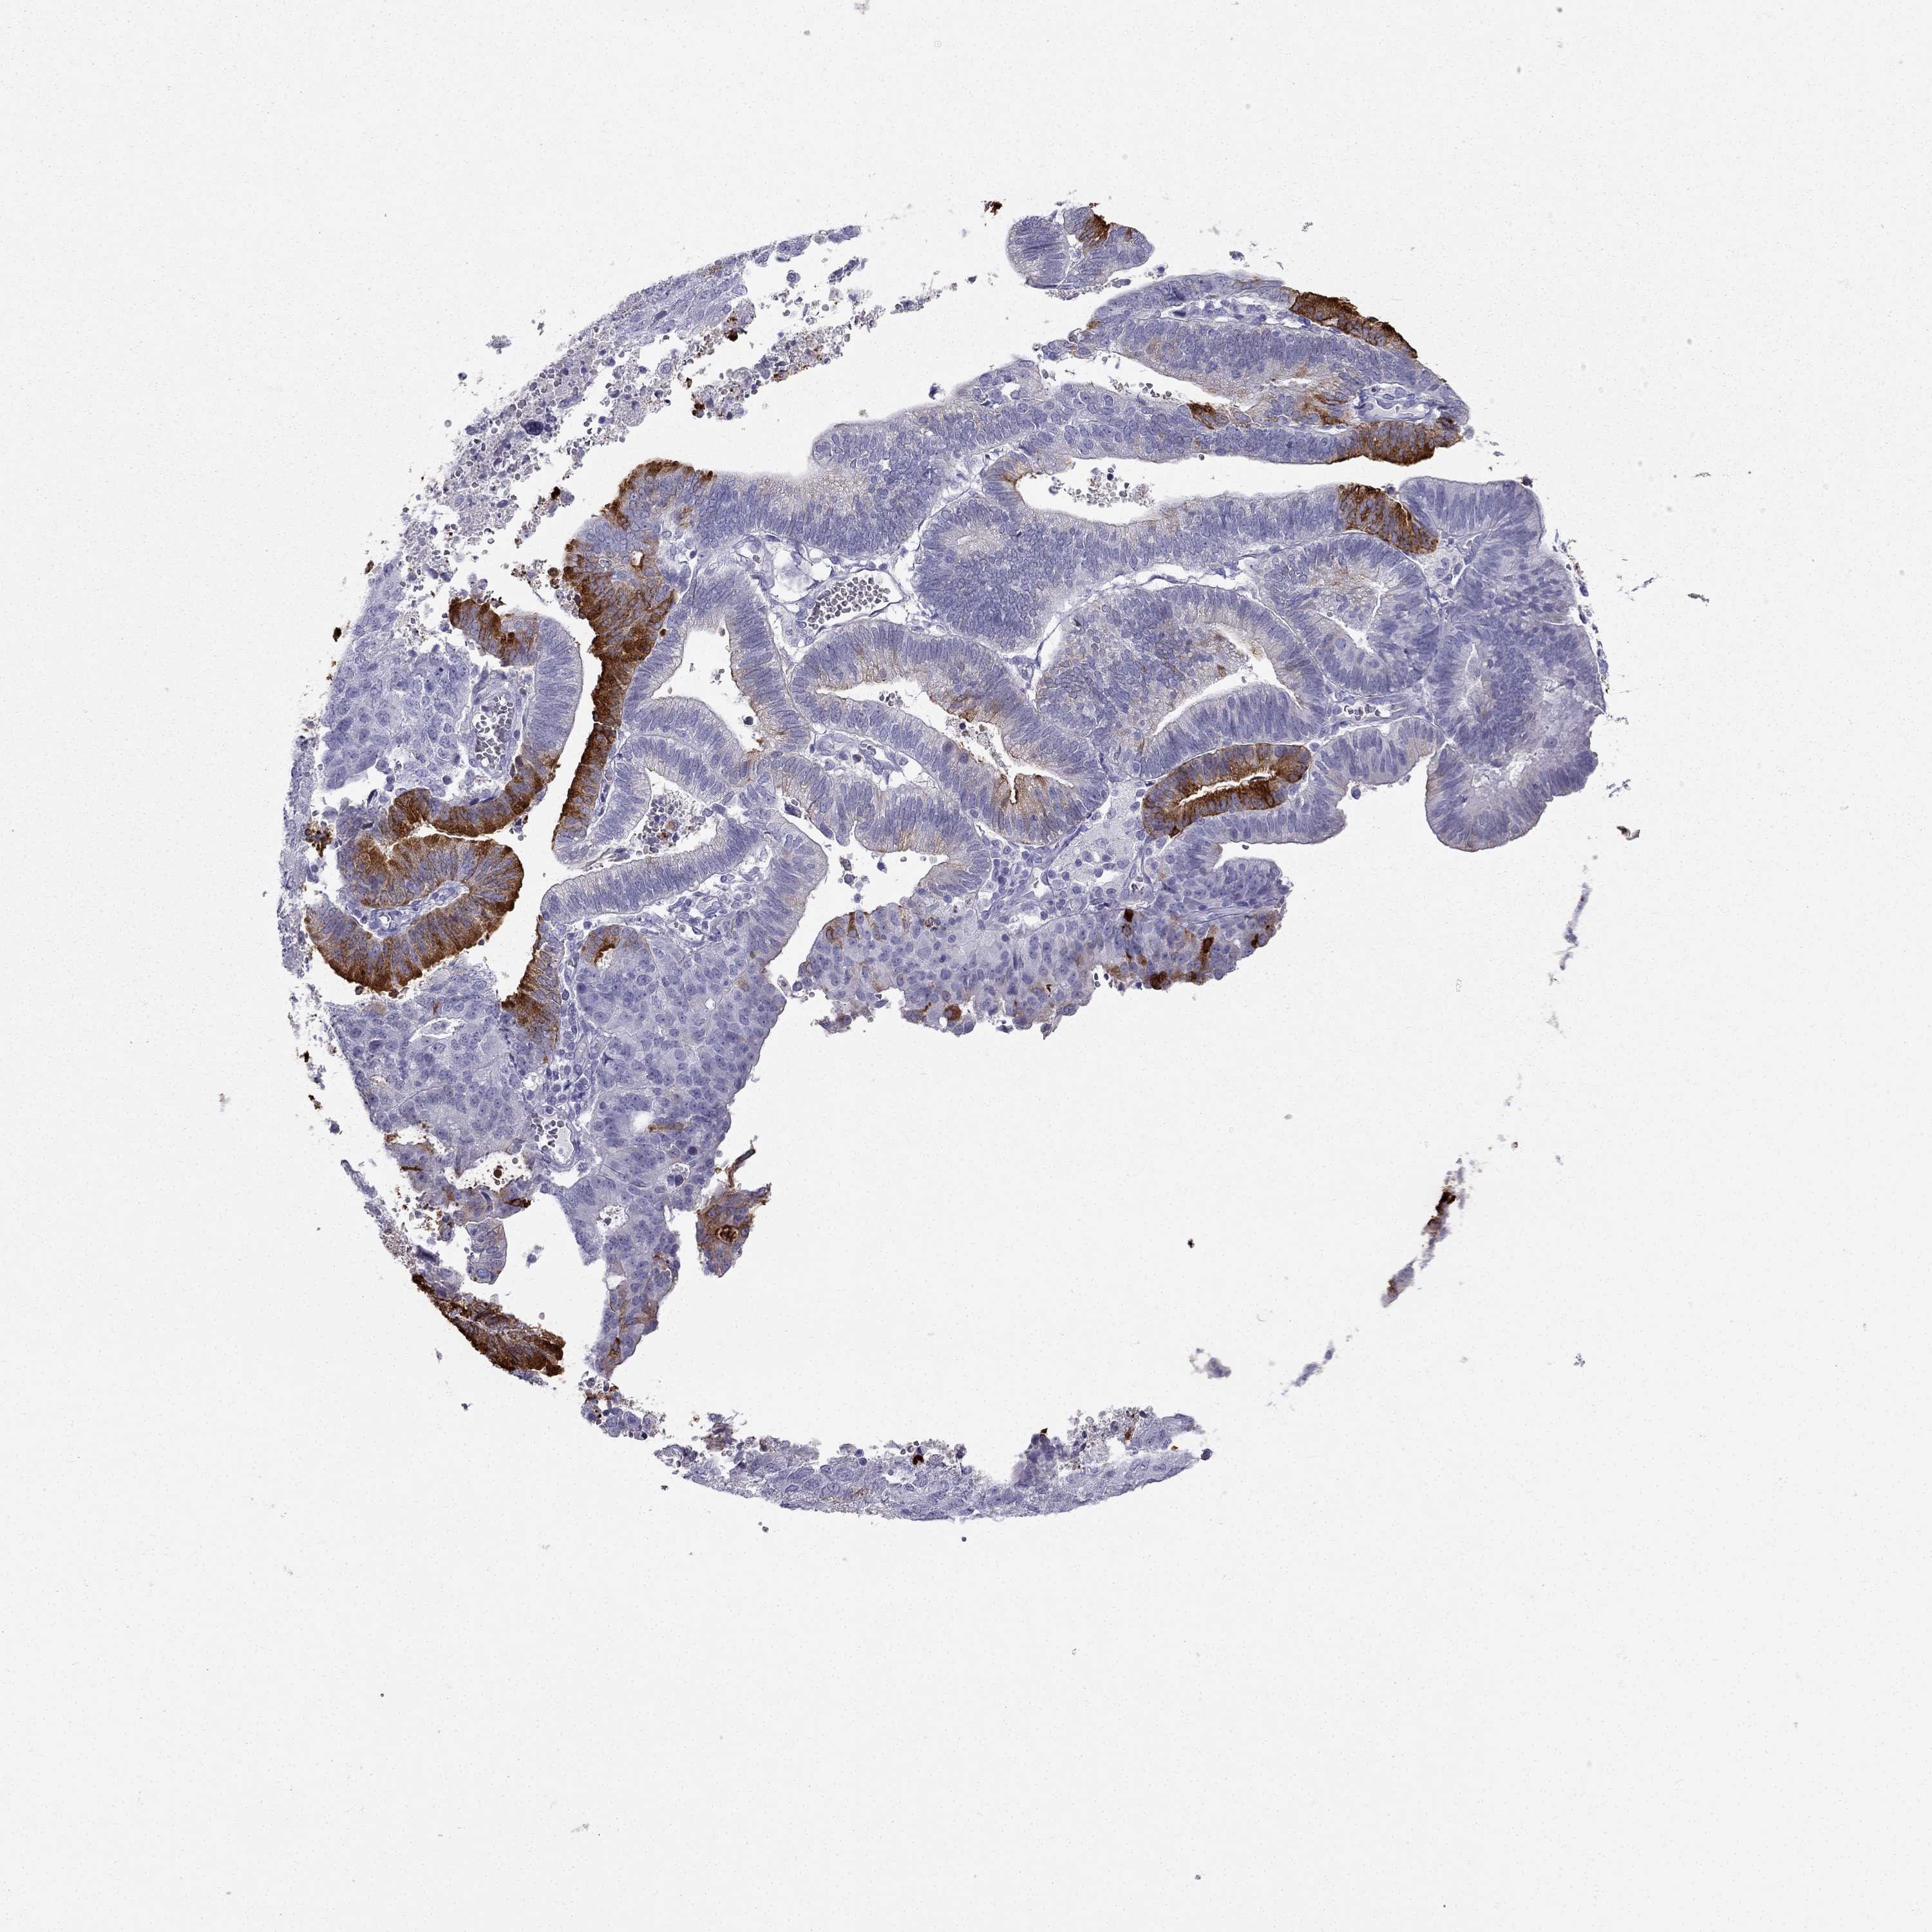

ENDOMETRIAL CANCER - Protein expressioni

A mouse-over function shows sample information and annotation data. Click on an image to view it in a full screen mode. Samples can be filtered based on level of antibody staining by selecting one or several of the following categories: high, medium, low and not detected. The assay and annotation is described here.

Note that samples used for immunohistochemistry by the Human Protein Atlas do not correspond to samples in the TCGA dataset.

Antibody stainingi

Antibody staining in the annotated cell types in the current human tissue is reported as not detected, low, medium, or high, based on conventional immunohistochemistry profiling in selected tissues. This score is based on the combination of the staining intensity and fraction of stained cells.

Each image is clickable and will lead to virtual microscopy that enables deeper exploration of all samples and also displays staining intensity scores, fraction scores and subcellular localization as well as patient and tissue information for each sample.

Antibody HPA035464

Antibody CAB020681

Staining

High

Medium

Low

Not detected

Intensity

Strong

Moderate

Weak

Negative

Quantity

>75%

75%-25%

<25%

None

Location

Nuclear

Cytoplasmic/membranous

Cytoplasmic/membranous,nuclear

Adenocarcinoma, NOS